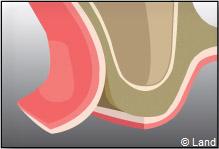

LES COMBLEMENTS SOUS-SINUSIENS

Ce comblement osseux est réalisé avant ou en même temps que la pose des implants.

L’intervention est réalisée sous anesthésie locale. Dans cet exemple le forage intéresse la paroi latérale du sinus.